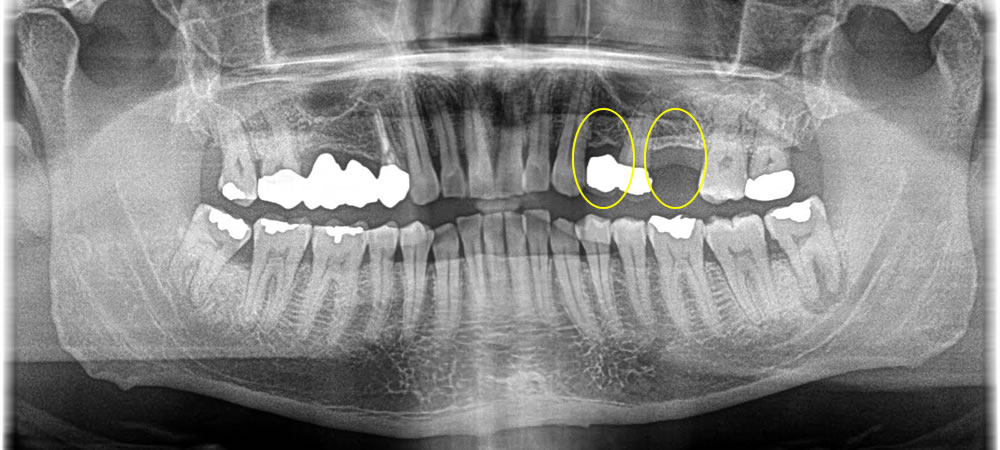

重症化した虫歯を抜歯後にインプラントで治療した症例

年齢

30代

性別

男性

症例を見る